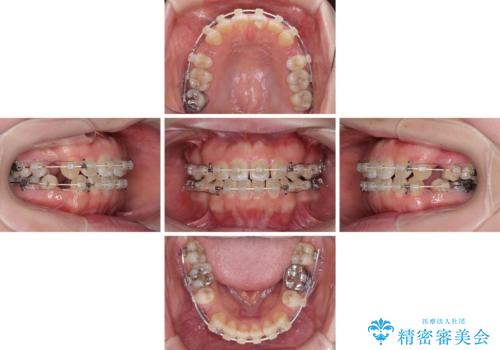

- 審美装置

- 2年4ヶ月

- 口元の膨らみが気になるとのことで来院された患者様です。

非抜歯で口元の突出感を少し改善させる治療も提案しましたが、最大限口元を引っ込めたいとのことでした。

上下左右第一小臼歯4本を抜歯し、ワイヤー装置により矯正治療を行うこととしました。

治療は順調に進み、予定された期間で終了することができました。

装置除去後には、スッキリとした口元となり、大変満足していただきました。